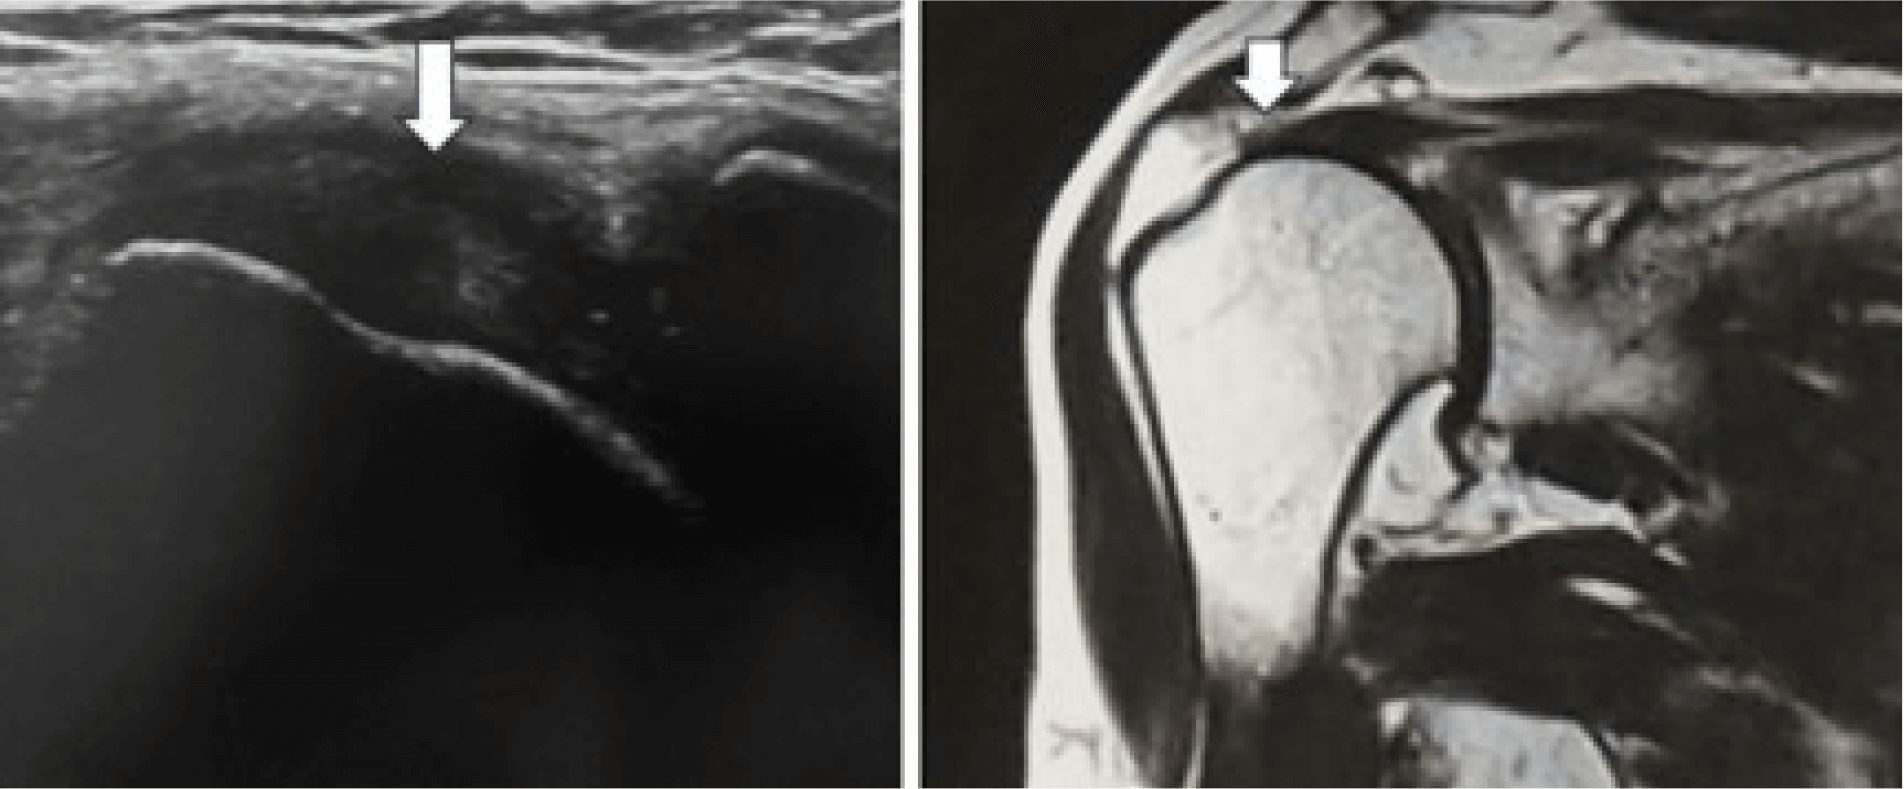

似たような症状の病気に肩の痛みと肩関節の可動域制限を伴う五十肩があります。腱板断裂と五十肩とを臨床的に鑑別するのは困難なことが多く、肩関節エコーや肩関節MRIで腱板が断裂している所見を確認する必要があります。

腱板断裂の肩関節エコーと肩関節MRI

(矢印:断裂部)